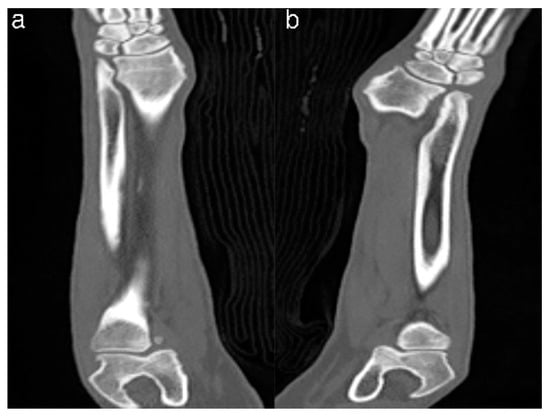

2.1. Case Presentation and Imaging